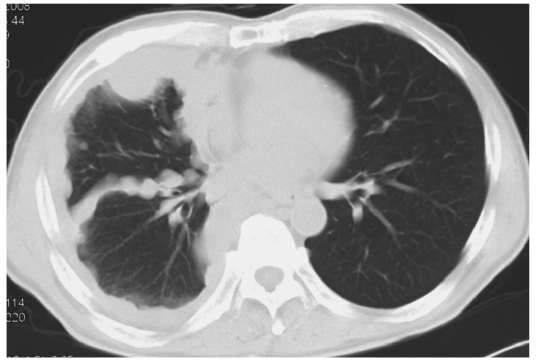

胸膜中皮腫の典型的なCT画像(T2)

葉間胸膜を含め、すべての胸膜が全周性に肥厚している。T2期胸膜中皮腫の典型像である。